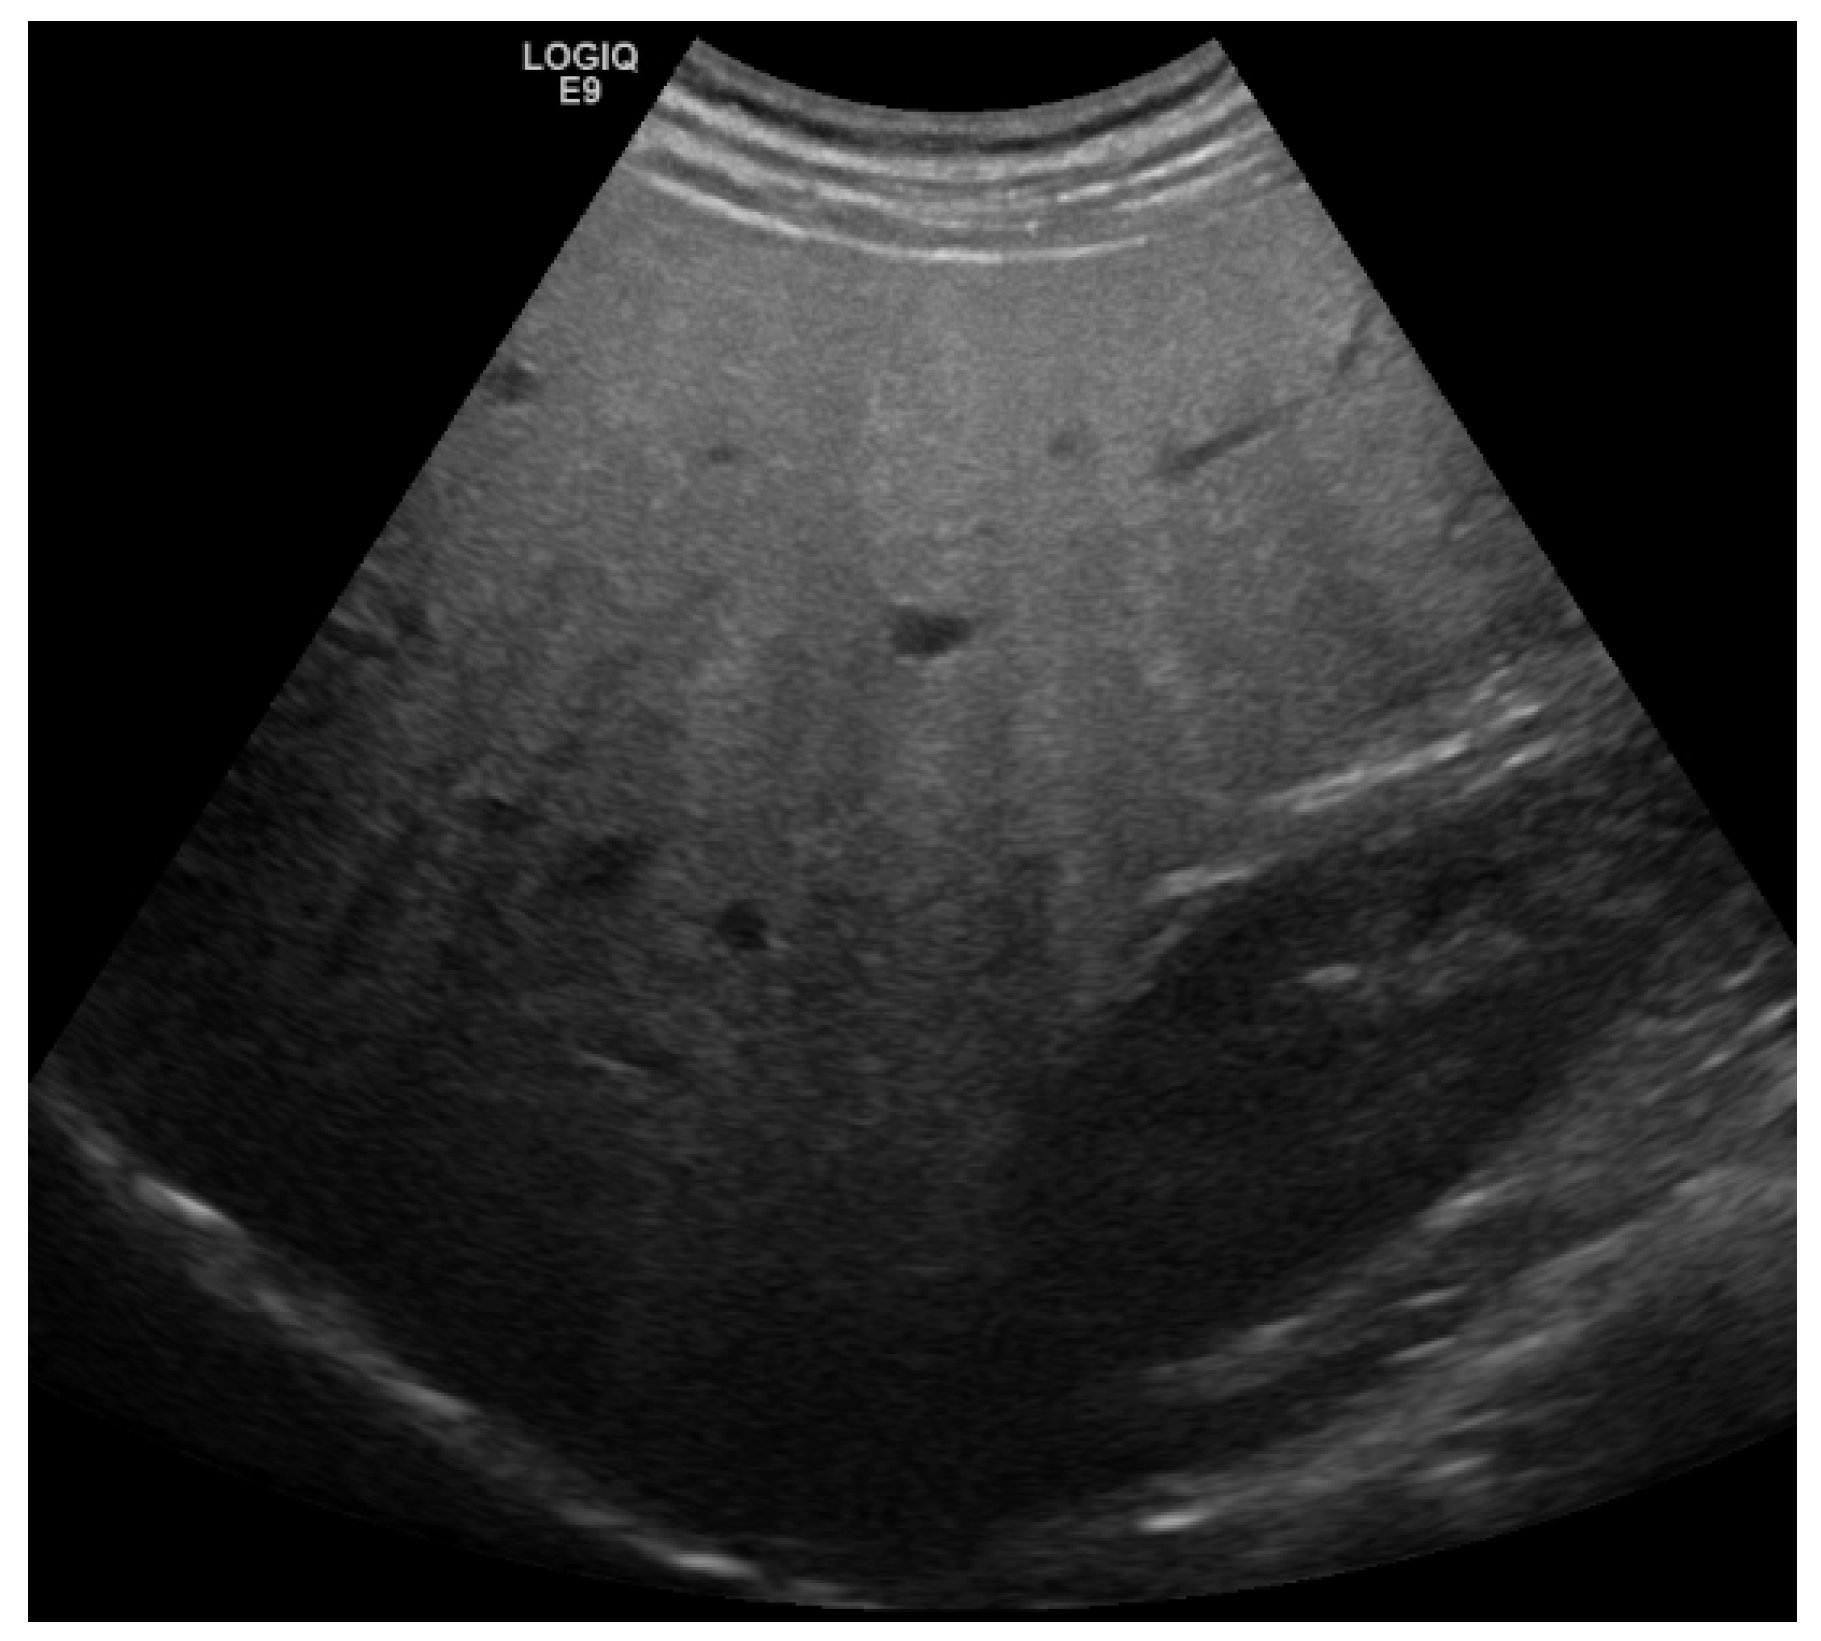

2. Detection and Graduation of Hepatic Steatosis